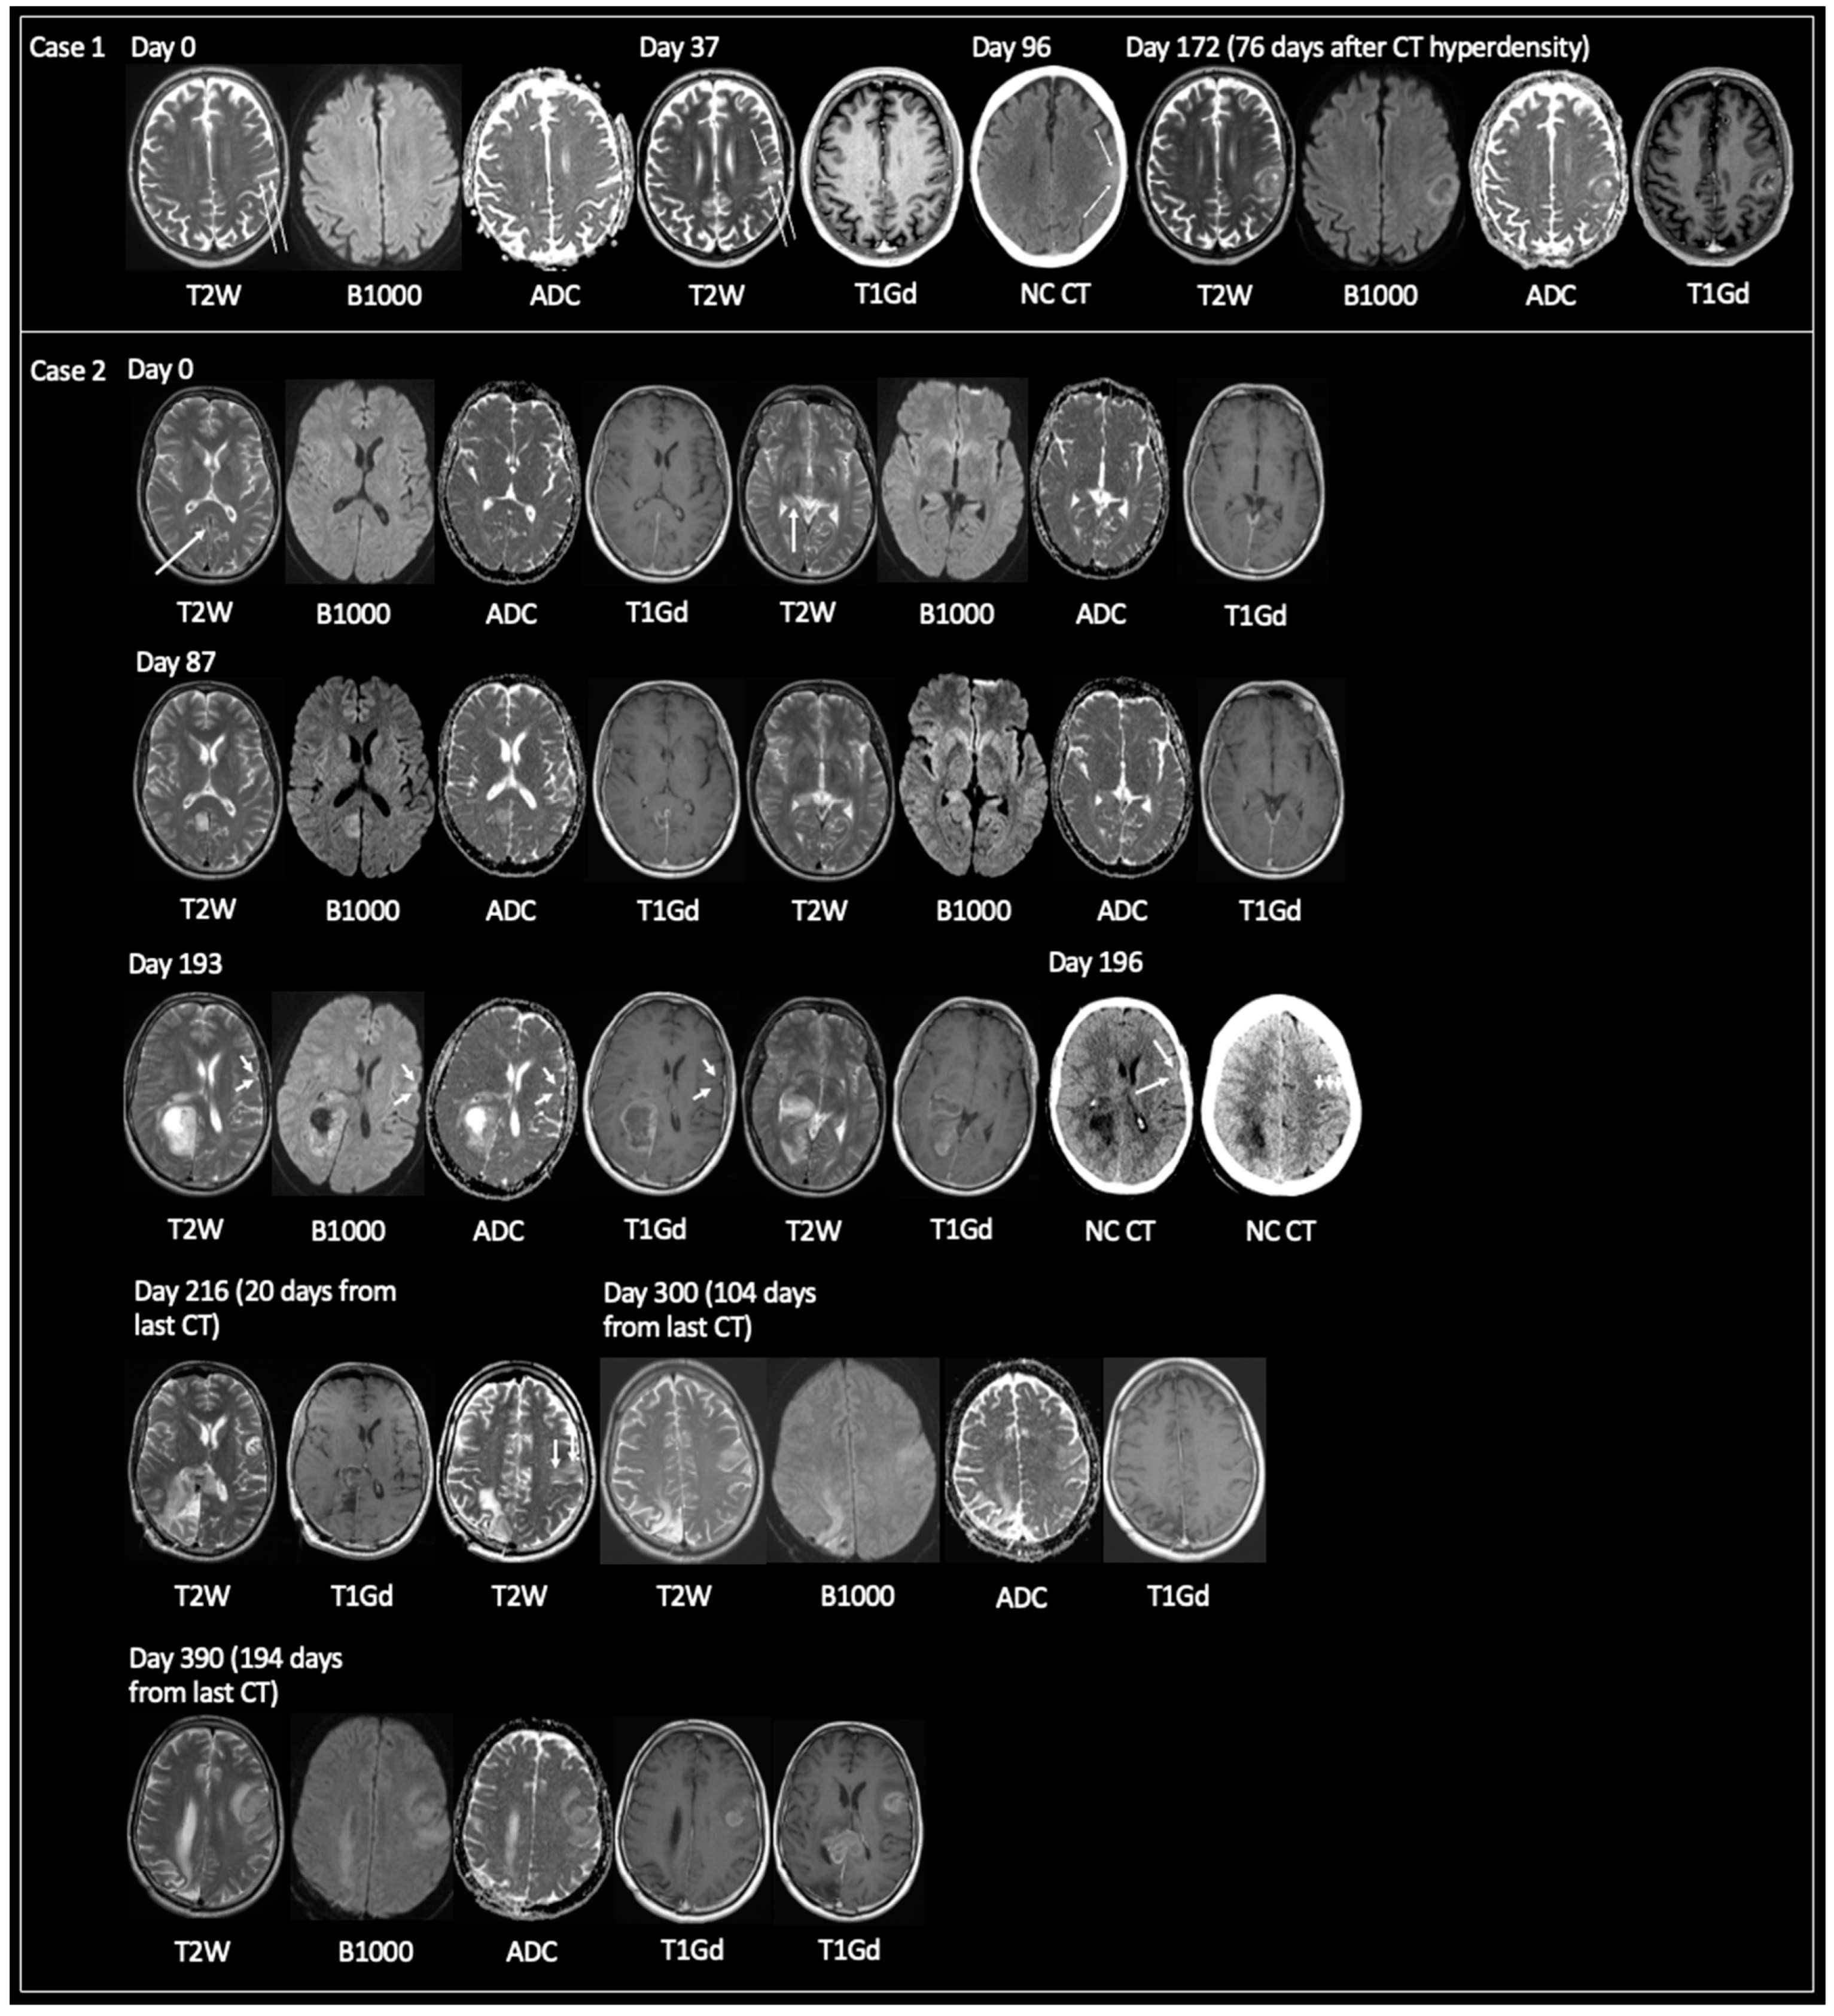

For 18/84 lesions, the earliest imaging features of GBM were T2 hyperintensity (n = 16) and CT hypodensity (n = 2). 13/16 T2 hyperintense lesions had accompanying DWI, and no lesion showed reduced diffusivity. 11/16 had T1Gd: 10 had no enhancement; 1 had a tiny dot of nodular enhancement. 7/18 lesions later showed T2 iso. Mean time from T2 hyperintensity/CT low density (n = 18) to TRA GBM = 173 days (43–537); solitary lesions only (n = 3) = 140 days (43–267); >1 locus only (n = 15) = 179 days (69–537). Figure 4 displays examples of lesions passing through phases of T2 hyperintensity to T2 iso/CT hyperdensity to TRA GBM.

Figure 4.

Examples of early GBM progressing through T2 hyperintensity to T2 iso and CT hyperdensity prior to showing TRA GBM. Case 1: 68-year-old male presented with dysphasia at day 96 leading to unenhanced CT investigation, which showed a solitary hyperdense lesion in the anterolateral aspect of the left parietal lobe, bordering the left supramarginal gyrus. MRI at day 172 showed TRA GBM with central necrosis and peripheral enhancement. MRI at day 0 obtained for an 8-week history of left-sided hearing loss revealed subtle cortical expansion at the site of future GBM (arrows) with no reduced diffusivity. On MRI day 37 the cortical expansion was more apparent showing relative growth to day 0. Case 2: 59-year-old male with progressively worsening headaches. MRI day 0 showed small foci of T2 signal hyperintensity in the cortex of the right precuneus (small arrow) and within the posterior aspect of the right parahippocampal gyrus (long vertical arrow). Neither the focus of T2 signal hyperintensity showed reduced diffusivity nor enhancement. Note the smooth dural thickening and enhancement on the T1Gd images. MRI day 87 showed interval growth of the lesion in the right precuneus with some central necrosis and peripheral enhancement. The lesion in the right parahippocampal gyrus had also grown relative to day 0 and continued to show facilitated diffusion and nonenhancement. The working diagnosis at the time of day 0 and day 87 was granulomatosis with polyangiitis, as the patient was ANCA positive and had no other known cause for dural enhancement. MRI day 193 showed growth at both lesion sites with TRA GBM. Note the new small ovoid focus of cortical T2 iso in the left inferior frontal gyrus (arrows), showing concomitant reduced diffusivity but no enhancement. An unenhanced CT obtained 3 days later, on day 196, showed corresponding CT hyperdensity in the lesion in the left inferior frontal gyrus and this subsequently developed into TRA GBM on MRI day 216. Note also the cortical T2 iso-lesion laterally in the posterior aspect of the left frontal lobe on MRI day 216 (3 vertical arrows), not clearly represented on CT day 196 (3 vertical arrows). This subsequently progressed to TRA GBM on MRI day 390 after showing growth and T2 iso signal on MRI day 300 with concomitant high B1000 signal but without enhancement (MRI day 300 was obtained 2 week after the patient’s third cycle of adjuvant TMZ—no RT was given as the patient declined whole brain RT, which was deemed the only valid RT option). Additionally, note TRA GBM within the splenium of the corpus callosum on MRI day 390 representing local progression of the original lesion (3 weeks following the patients sixth cycle of adjuvant TMZ). TRA GBM—typical radiological appearance of glioblastoma, NC CT—non-contrast CT, C+ CT—intravenous contrast-enhanced CT, T2W—T2-weighted, B1000—DWI, ADC—apparent diffusion coefficient map of DWI, T1Gd—T1-weighted post-gadolinium, RT—radiotherapy, TMZ—temozolomide, ANCA—antineutrophilic cytoplasmic antibody.